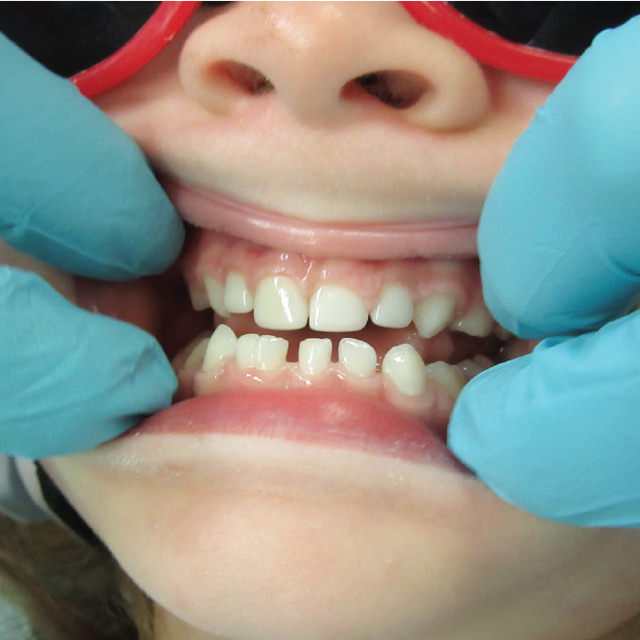

Patients with class-three malocclusions commonly present some of the most challenging cases we see. Often their occlusions also are complicated by deep underbites or crossbites leading to frequent fractures in restorative materials such as composite crowns when they are used as part of the treatment.

Due to Zirconia’s strength and superior esthetics, Zirconia crowns are often the best and most reliable choice to use in restoring these challenging cases. The first thing to consider when planning treatment to restore an anterior tooth in a patient with cross-bite is whether the case is a dental or skeletal class-three malocclusion. This determination will dictate the course of treatment. Let me explain.